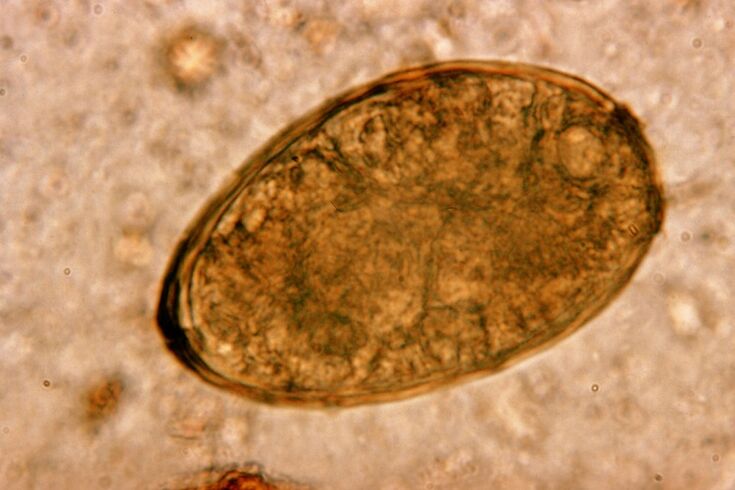

Fluke lives in the body in the lungs, forming cysts in the bronchi.It occurs when the member eats crayfish and crayfish infected with the parasite.Once in the gastrointestinal tract, the lung fluke penetrates the peritoneum and reaches the lungs through the diaphragm, which causes a persistent cough in the patient.

A small helminth lung belonging to the class Trempates, "abbreviation" to parasitize specifically in the lungs.For example, it causes a more serious problem in the respiratory system than, for example, roundworms.

At the site of localization, infiltrates appear and bleeding occurs, as a result of which worms, dead parasites and lung tissues are filled with decayed metabolites.Damage from the lung fluke is exacerbated by its long liver and ability to live in the host's body for up to 20 years.